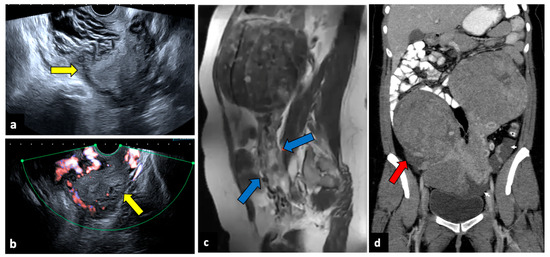

Review

Gynaecological Causes of Acute Pelvic Pain: Common and Not-So-Common Imaging Findings

by Paolo Niccolò Franco, Alejandra García-Baizán, María Aymerich, Cesare Maino, Sofia Frade-Santos, Davide Ippolito and Milagros Otero-García

Life 2023, 13(10), 2025; https://doi.org/10.3390/life13102025 - 9 Oct 2023

Cited by 14 | Viewed by 11064

In female patients, acute pelvic pain can be caused by gynaecological, gastrointestinal, and urinary tract pathologies. Due to the variety of diagnostic possibilities, the correct assessment of these patients may be challenging. The most frequent gynaecological causes of acute pelvic pain in non-pregnant [...] Read more.

In female patients, acute pelvic pain can be caused by gynaecological, gastrointestinal, and urinary tract pathologies. Due to the variety of diagnostic possibilities, the correct assessment of these patients may be challenging. The most frequent gynaecological causes of acute pelvic pain in non-pregnant women are pelvic inflammatory disease, ruptured ovarian cysts, ovarian torsion, and degeneration or torsion of uterine leiomyomas. On the other hand, spontaneous abortion, ectopic pregnancy, and placental disorders are the most frequent gynaecological entities to cause acute pelvic pain in pregnant patients. Ultrasound (US) is usually the first-line diagnostic technique because of its sensitivity across most common aetiologies and its lack of radiation exposure. Computed tomography (CT) may be performed if ultrasound findings are equivocal or if a gynaecologic disease is not initially suspected. Magnetic resonance imaging (MRI) is an extremely useful second-line technique for further characterisation after US or CT. This pictorial review aims to review the spectrum of gynaecological entities that may manifest as acute pelvic pain in the emergency department and to describe the imaging findings of these gynaecological conditions obtained with different imaging techniques. Full article